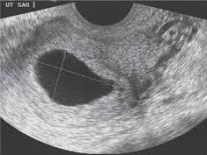

El tratamiento inicial es reposo en cama (que dependiendo del caso puede o no ser absoluto), hidratación, suspender las relaciones sexuales y acudir con el especialista para confirmar el diagnostico a través de ultrasonido y el examen médico especializado que permita saber que está ocasionando el problema y poder establecer el mejor manejo.